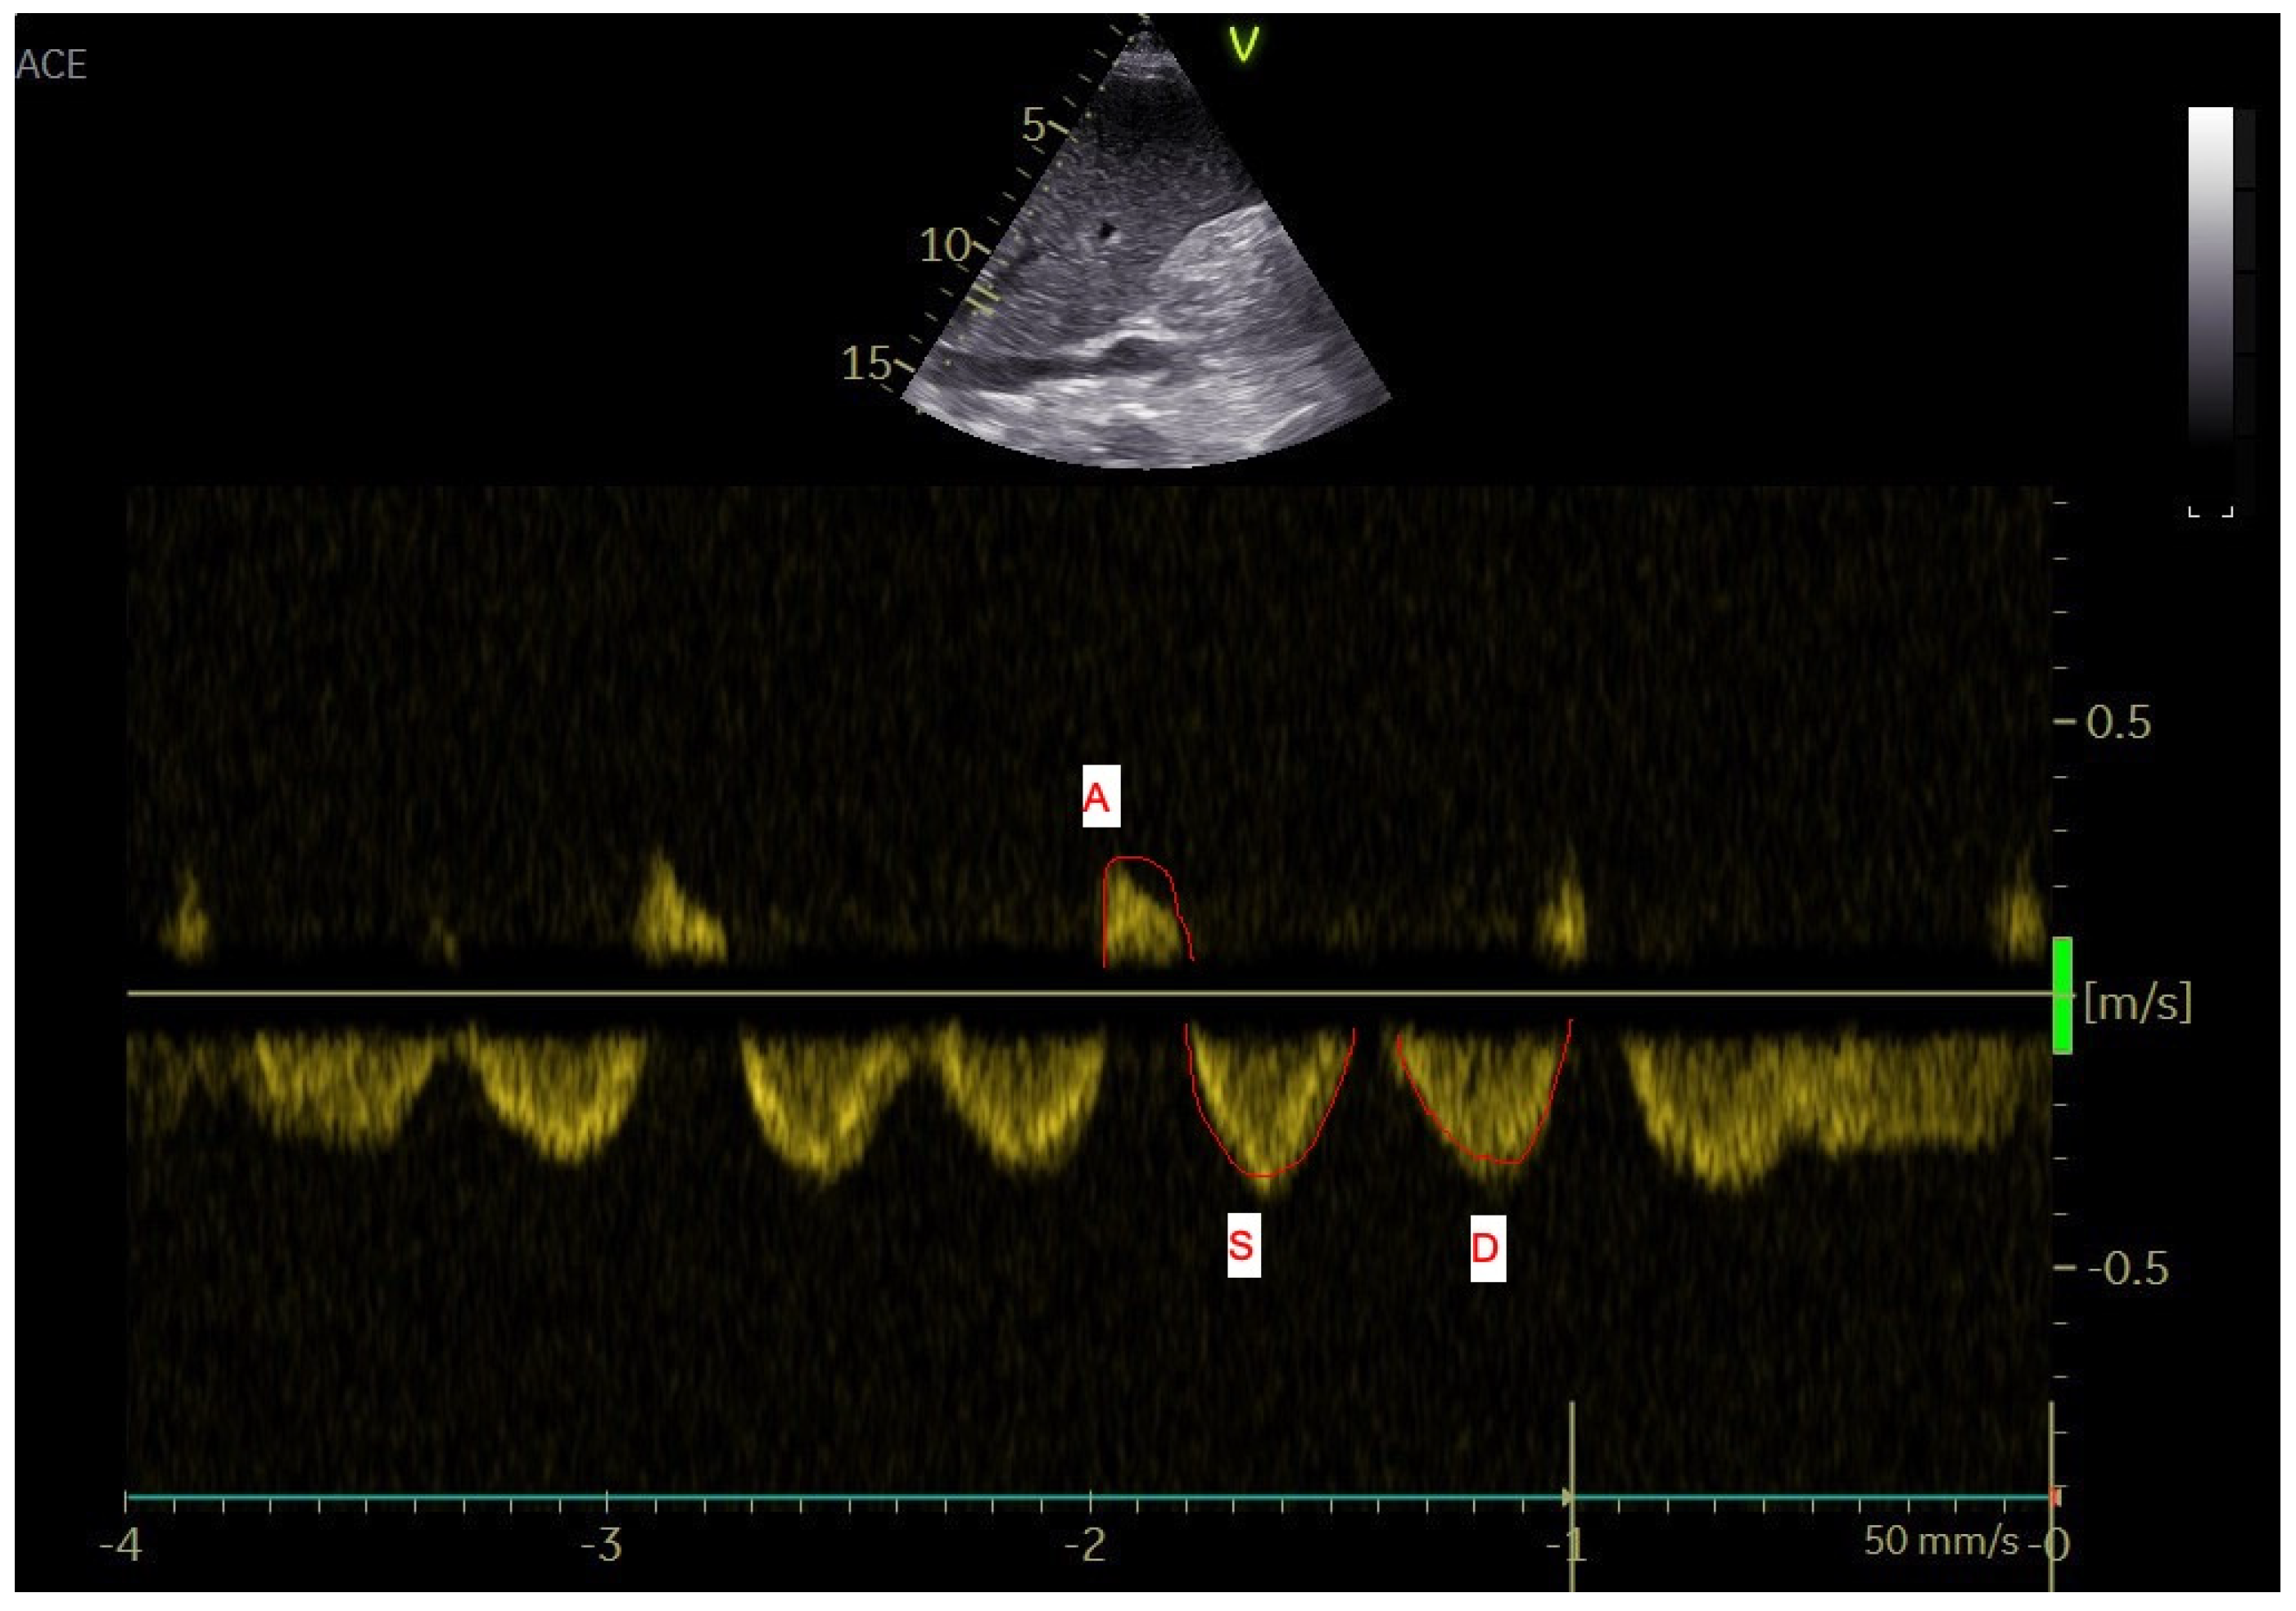

2.3. Analyses of the Hepatic Veins

Figure 3. Doppler ultrasound analysis of the hepatic veins–maximum velocity and velocity-time integral were measured (a line was adjusted to the maximum point and continuous wave Doppler’s spectral curve was calculated by the machine. A and V waves are retrograde, S and D are anterograde waves).